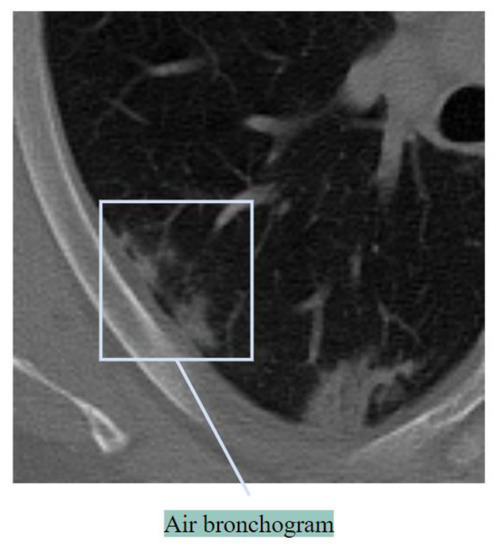

Air Bronchogram

An air bronchogram refers to a bronchus that is excessively filled with air. This feature is an indication of advanced disease [21]. Figure 6 shows air bronchogram regions of an abnormal lung.

Figure 6. Air bronchogram.

An air bronchogram can be an indication of lung disorders like tuberculosis and pneumonia [27]. In classifying lung cancer, air bronchogram can also be important. An effective process of highlighting these anomalies should be considered.